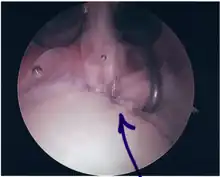

Repair of SLAP Tear

Arthroscopic SLAP Lesion (type 2) repair

Following inspection and determination of the extent of injury, the basic labrum repair is as follows.

• The glenoid and labrum are roughened to increase contact surface area and promote re-growth.

• Locations for the bone anchors are selected based on number and severity of tear. A severe tear involving both SLAP and Bankart lesions may require seven anchors. Simple tears may only require one.

• The glenoid is drilled for the anchor implantation.

• Anchors are inserted in the glenoid.

• The suture component of the implant is tied through the labrum and knotted such that the labrum is in tight contact with the glenoid surface.